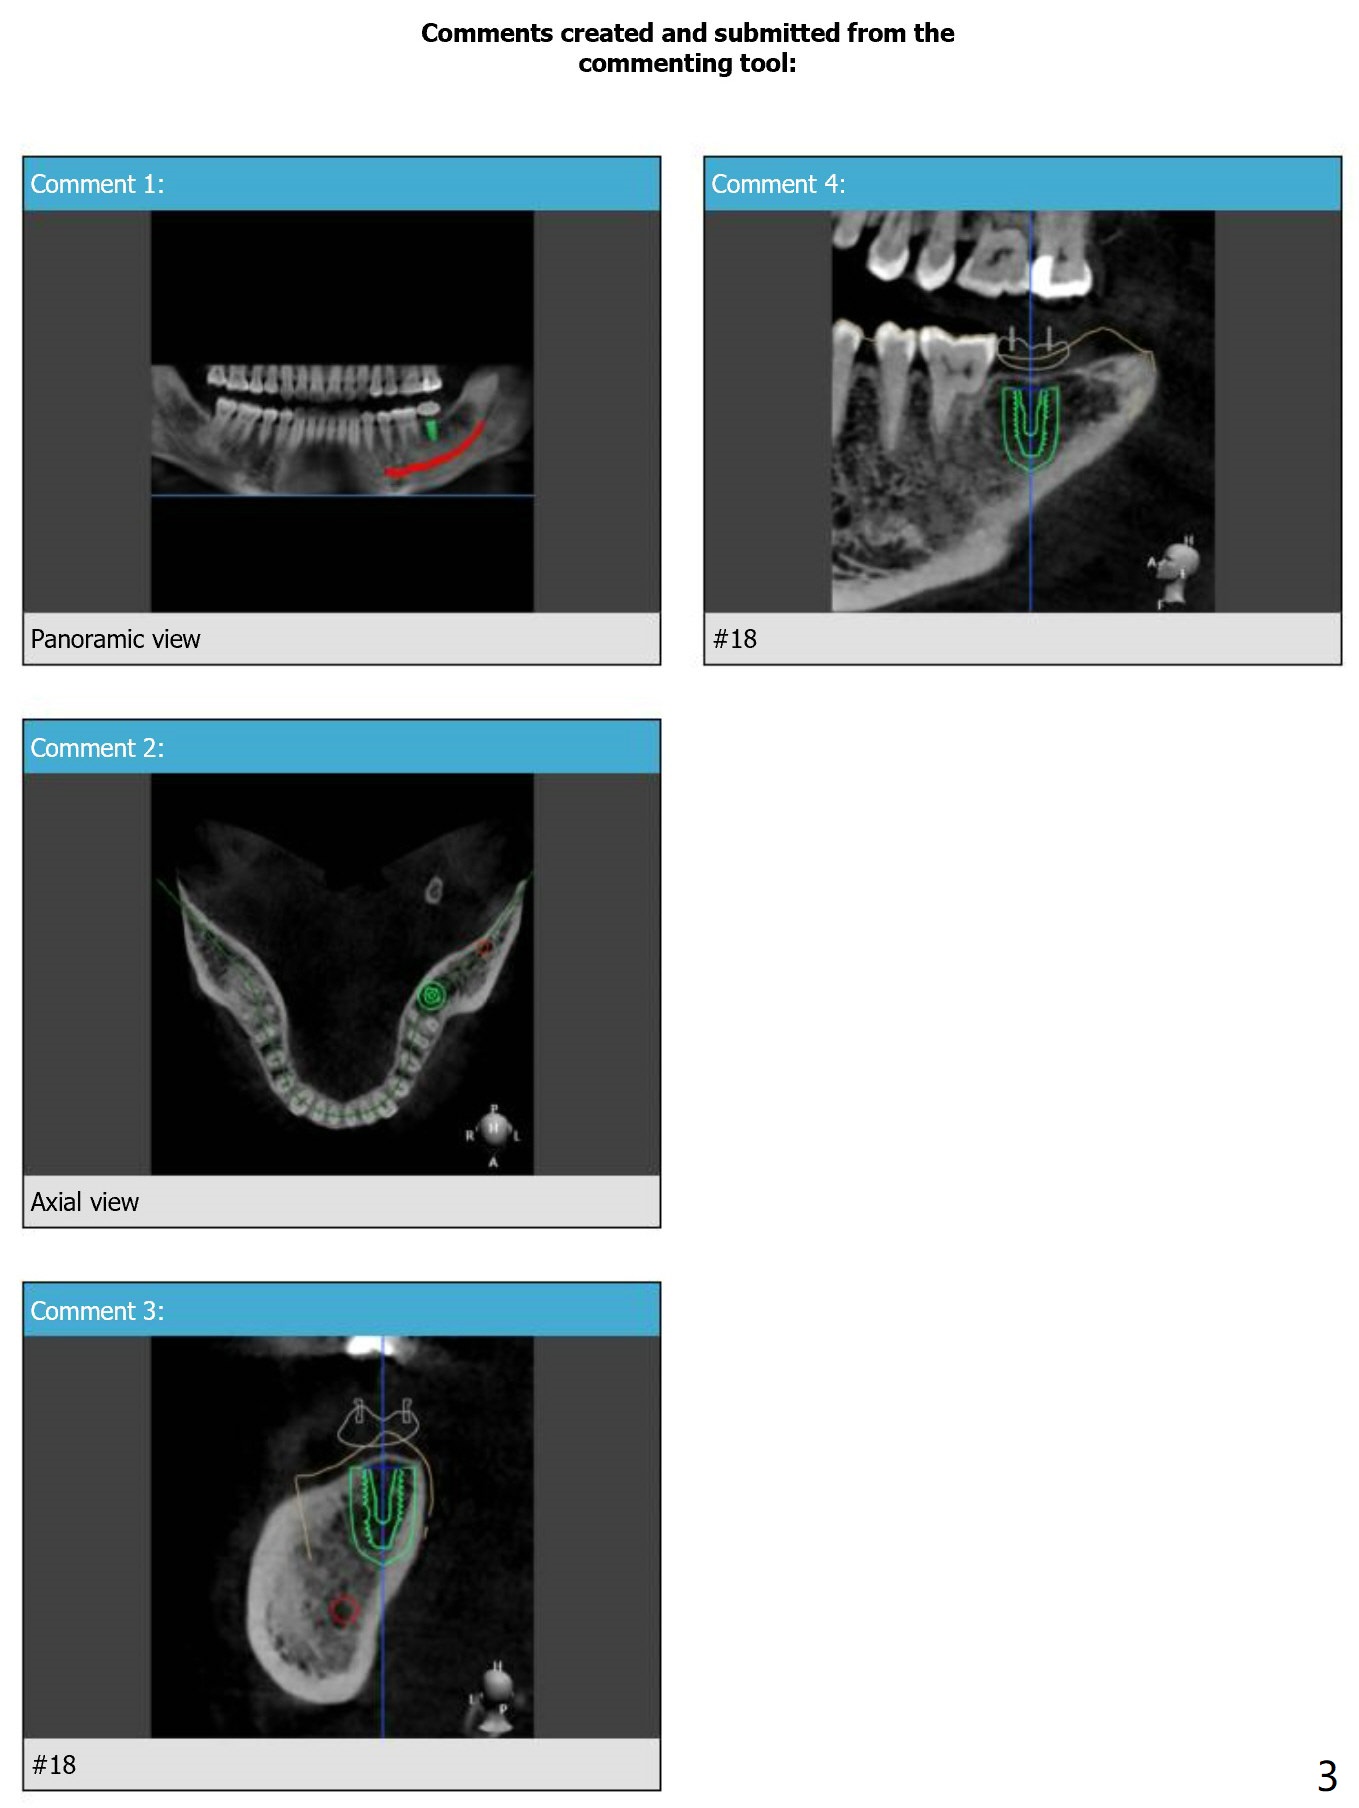

Guide Design

Return to Lower Molar Immediate Implant, Armaments, Surgery